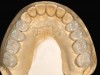

Fig 20. Postoperative occlusal view of maxillary arch with full-contour monolithic high-translucent zirconia restorations on all teeth.

Figure 20

A 40-year-old patient presented with the chief complaint: “My teeth are cracking, and I would like to have my original bite.” Dental findings included Class I occlusion with slight misalignment between teeth Nos. 8 and 9. Generalized severe occlusal wear and slight Class I mobility of teeth Nos. 23 to 26 were noted. Caries lesions were found on teeth Nos. 2, 4, 6, 8, 9, and 14 and abfraction lesions on teeth Nos. 4, 5, 10, 11, 13, 20, and 21. Figure 1 through Figure 3 depict the preoperative situation. Full-mouth rehabilitation was suggested. The goals for the restorative treatment were management of erosive etiology, conservation of tooth structure, and long-term protection of the restorations. A diagnostic wax-up was instrumental in determining functional and esthetic treatment goals and establishing new anterior guidance (Figure 4). A comprehensive, step-by-step treatment approach was applied, which, after periodontal pretreatment, caries control, and provisionalization, included definitive preparation (Figure 5) and restoration of the maxillary anterior teeth to establish anterior occlusal guidance. CAD/CAM–fabricated full-contour monolithic high-translucent zirconia crowns (Katana™ UTML Ultra Translucent Multi-Layered, Kuraray Noritake Dental, kuraraynoritake.com) were fabricated (Figure 6 and Figure 7) and cemented with self-adhesive resin cement (Panavia SA, Kuraray Noritake Dental). Figure 8 demonstrates the cemented anterior crowns and refined conservative preparations of posterior teeth, which were performed with minimal tooth-structure removal. High-translucent monolithic zirconia onlays and crowns were fabricated (Katana Zirconia UT, Kuraray Noritake Dental) (Figure 9 to Figure 12). The posterior restorations were adhesively bonded following the APC zirconia-bonding concept. APC-Step A involved air-particle abrasion with 50-μm aluminum oxide at 1.5 bar with a chairside microetcher (Figure 13), followed by application (APC-Step P, Figure 14) of a special ceramic primer (ClearfilTM Ceramic Primer, Kuraray Noritake) with adhesive phosophate monomers (MDP). Relative moisture and contamination control was achieved with cotton rolls and retraction cords. Rubber dam placement, which is always preferred, was difficult in this situation. The enamel surfaces of the abutment teeth were selectively etched (Figure 15) with 35% phosphoric acid (K-Etchant Gel, Kuraray Noritake Dental) and the dentin conditioned (Figure 16) with a self-etch dentin primer (Panavia V5 Tooth Primer, Kuraray Noritake Dental). A dual-cure adhesive resin (Panavia V5 Paste Universal, Kuraray Noritake Dental) was dispensed directly into the restorations with an automix syringe. The restorations were inserted, and excess cement was carefully removed (Figure 17 and Figure 18) before light polymerization (Figure 19). Postoperative views depict the treatment outcome (Figure 20 to Figure 22).